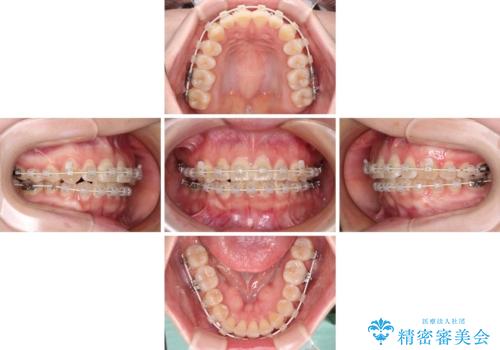

【モニター】前歯のデコボコを目立たないワイヤー装置で短期間矯正治療

- 審美装置

- 10ヶ月

- 上下前歯のデコボコを気にして来院された患者様です。

ワイヤー矯正でもインビザライン矯正でも対応可能でしたが、インビザラインでの自己管理の煩わしさを避けるため、ワイヤー装置にて矯正治療を行うこととしました。